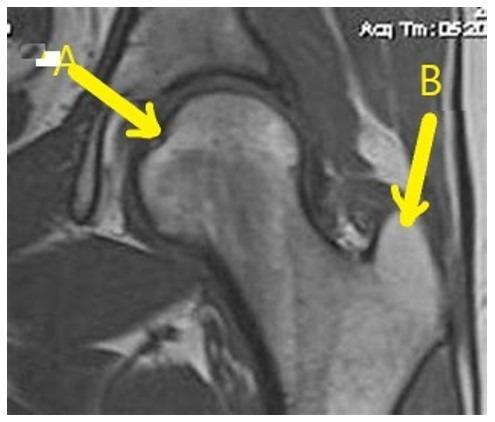

lesser trochanter

Greater trochanter

Which letter is the Anterior acetabular labrum?

Acetabular labrum